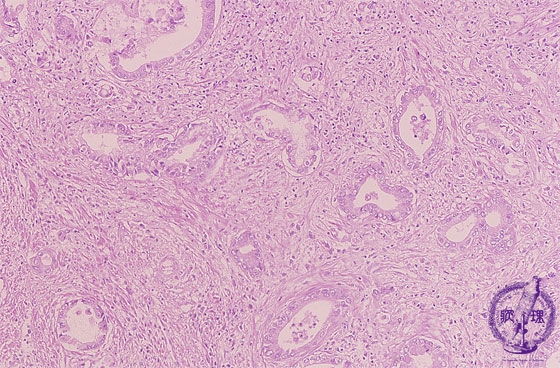

• š(13)Intrahepatic bile duct cancer (adenocarcinoma)

Microscopic image (HE stain, intermediate power): Moderately differentiated tubular adenocarcinoma consisting of columnar to cuboidal epithelium with abundant fibrous stroma.